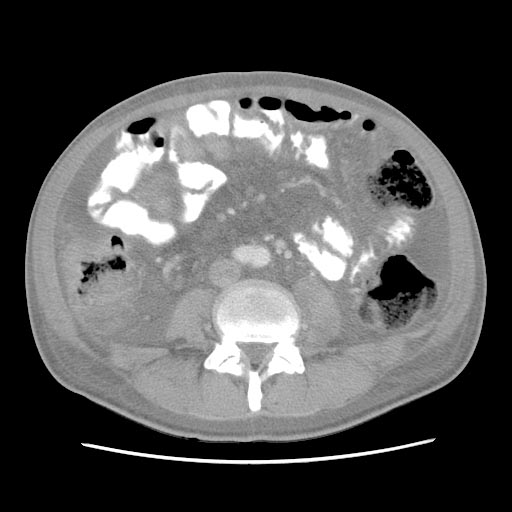

Анасарка мкб

Анасарка мкб 89 фотографий